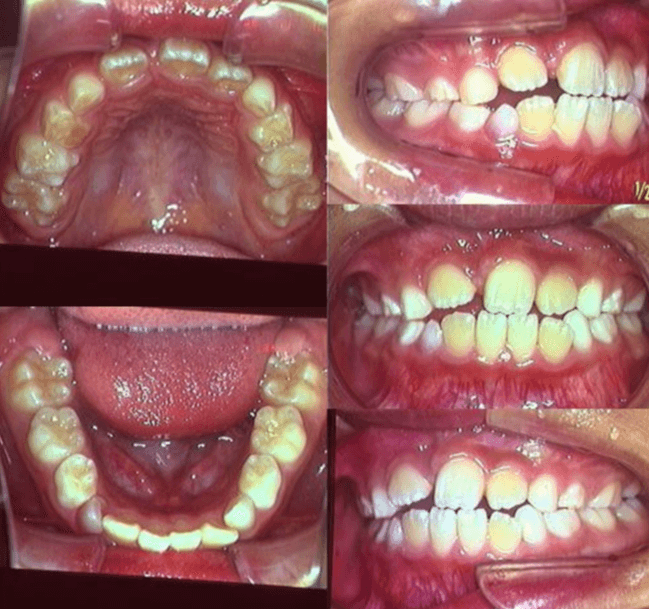

早期矯正治療 埋伏歯症例②

主訴 | 上顎前歯の位置異常に不安を抱え、歯並びと将来的な咬合状態を整える目的で来院された患者様です。 特に左側の前歯(中切歯および側切歯)の萌出が確認できないことがきっかけとなりました。 |

---|---|

診断結果 | 8歳3か月の男児。 左上1番(中切歯)と左上2番(側切歯)が埋伏し、発育方向にも異常が認められました。加えて、一部先天性欠如も確認されており、歯列全体の成長に影響を及ぼす可能性があると診断されました。 |

治療内容 |

|

治療後の経過 | 動的治療後は3〜4か月ごとの定期検診を行い、上下顎の骨の成長や第二大臼歯の萌出状況を確認しながら、本格的な矯正治療を行う |

治療期間 | 動的治療期間:約5年10か月 |

治療費用 | 460,000円(税別) |